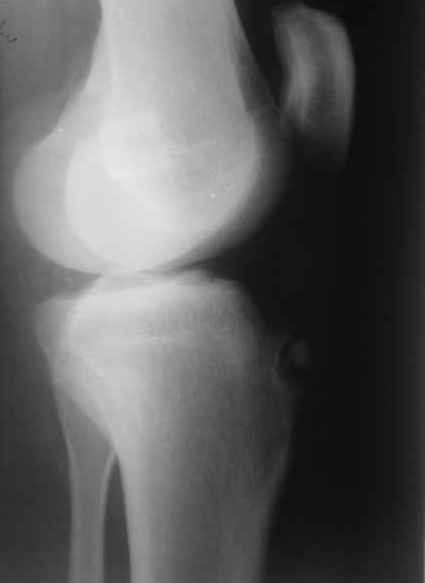

Здравствуйте, коллеги.Вопрос (как и предыдущий) опять из разряда "кислых" :)))Мужчина 30 лет. Жалобы на резкий отек и боли в коленном суставе.

Травму и значительные физические нагрузки исключает. На рентгене - некроз бугристости большого берца. На фоне иммобилизации конечности задней гипсовой шиной и назначения НПВС отек и боли чудесным образом купированы :)))) В анамнезе болезнь Озгуда-Шлаттера, благополучно отслужил в вооруженных силах. До сегодняшнего момента ничего не беспокоило. На снимке вижу отрыв некротически измененного участка бугристости берца. Разгибание в коленном суставе восстановлены. Встал вопрос о дальнейшей тактике лечения такого пациента. Отправить пациента к краевым кудесникам, либо можно обойтись своими силами? Операция? Консервативное лечение?-- С уважением, Заднепровский Никита Николаевич

Это диссекат, не отрыв.

А в данном случае индекс Блэкберн и Пилл 0.75.

Есть подозрение на пателла альта.